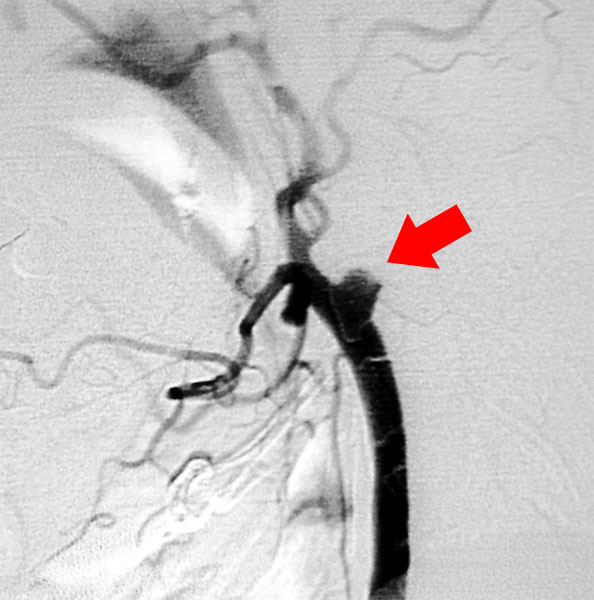

術中脳血管撮影

治療困難な大型動脈瘤や深部にある動脈瘤では顕微鏡観察だけでは完全なクリッピングができているのか、或いは動脈瘤の親血管が狭くなっていないかといった検討が十分にできないことがあります。そこで当科では術中血管撮影を行い、完全なクリッピングと、親血管の血流が保たれていることを手術中に確認し、手術の確実性、安全性を向上させています。